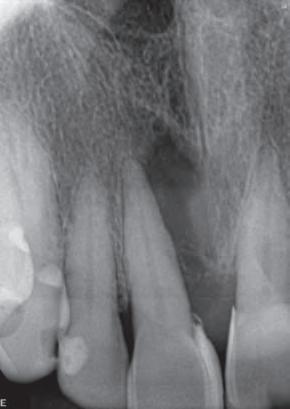

Imagen cedida por Dr. Vicente Rocha.

Prof. Dr. Warley Tavares

04/2017

Masculino

45 años

Periodontitis Apical Crónica.

O. 10 meses

Instrumentación con NiTi, Hipoclorito de Sodio 2,5%, medicación con Hidróxido de Calcio por 10 días.

Obturación con gutta percha y BIO-C® SEALER.

02/2018